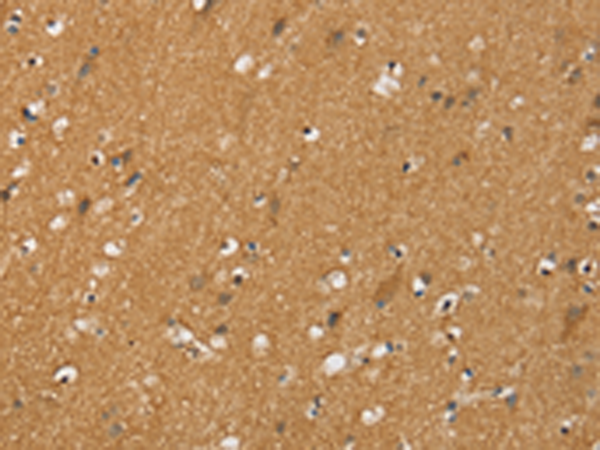

分类: 科研抗体货号: P12200别名: HND; B0AT1应用: IHC反应种属: Human